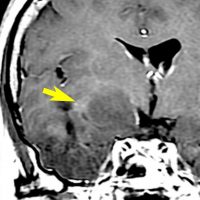

症候性てんかんのみで発症した右側頭葉と島回のグレード2オリゴです。左のT2,中央のフレアではグレード2びまん性星細胞腫と鑑別はできません。認知機能などは正常でした。

何と言っても診断的価値があるのは 石灰化 carcification です。左のCTの中央にみえる白い部分が石灰化です。この程度の石灰化でも診断的な価値があります。1p/19q codeletionがあるオリゴでした。病理では,均一な小型の円形核を有する細胞と多数の毛細血管 chickin-wire network がみられます。部分摘出後,放射線治療とテモゾロマイド化学療法でコントロールできています。